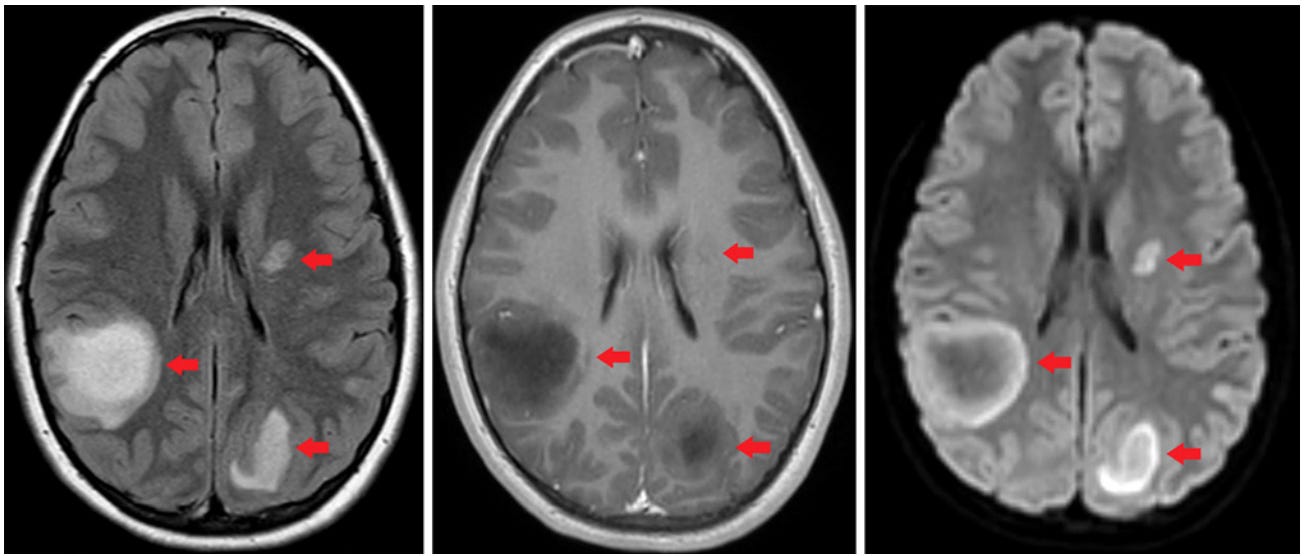

Florida - 10 year old girl developed Acute disseminated encephalomyelitis with autoimmune brain lesions after 2nd Pfizer COVID-19 mRNA jab, July 2022 (click here)